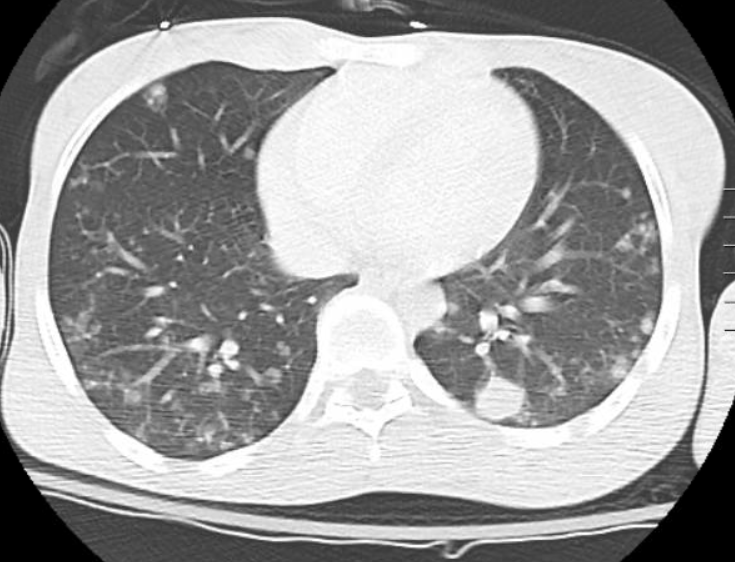

Later that month, the patient presented to our ED for the first time after being found to be minimally conversive at home. Per her family member, the patient had been largely asymptomatic with minor nausea prior to this acute change in mental status. The patient answered yes/no for all questioning with the exception of repeating the phrase “molar pregnancy.” Complete blood count, basic metabolic panel, and Covid-19 tests were normal. A qualitative UPT was negative, thyroid stimulating hormone was 0.01 mIU/L with free T4 of 5.4ng/dL, and urine drug screen was unremarkable. Vital signs were stable aside from sinus tachycardia in the low 100s. Within two hours the patient experienced a generalized tonic clonic seizure. CT head without contrast revealed 3.6x3.3x3.8cm left frontal intraparenchymal hematoma with significant vasogenic edema and a left to right midline shift (Figure 1). TVUS showed a complex intrauterine hypervascular structure. Abdominal CT reveled a markedly enlarged and heterogeneous appearing uterus concerning for malignant process of uterine etiology (Figures 2). An additional large multiloculated cystic structure was identified, centered at the left adnexa with differential diagnosis of complex ovarian cystic mass vs ovarian tumor vs hydrosalpinx. CT chest revealed innumerable nodules throughout the bilateral lungs concerning for metastatic disease (Figure 3). A quantitative b-HCG was >2.5 million with normal cancer markers (CEA of 1.9ng/mL, CA-125 26.80U/mL, AFP 3.7ng/mL), confirming the diagnosis of choriocarcinoma.

Figure 3 CT chest with contrast concerning for multiple lung metastasis from choriocarcinoma.